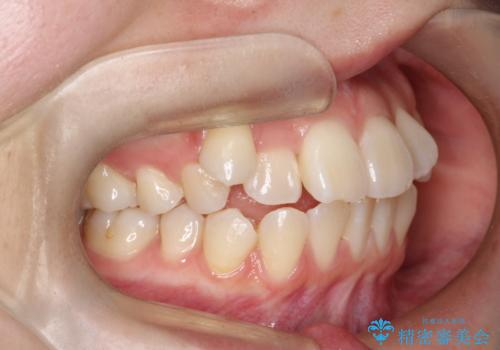

ハーフリンガル矯正|下顎前歯3本の特異症例を抜歯矯正で改善

- 患者様は下顎の前歯が3本しかないという特異な歯列を持ち、噛み合わせのバランスが崩れていました。上下の歯の本数が通常と異なるため、抜歯部位の選定が重要となるケースでした。診査の結果、歯の位置や咬合のバランスを考慮し、上顎の両側小臼歯2本と左下の小臼歯1本を抜歯することで、上下の噛み合わせを整える方針としました。矯正装置は、**目立ちにくいハーフリンガル(上顎は裏側矯正・下顎は表側矯正)**を採用しました。

まず、計画通りに抜歯を行い、歯列のスペースを確保しました。上顎は裏側矯正(リンガル)で目立たないように配慮しながら歯を後方へ移動し、下顎は表側矯正を使用して、3本の前歯の位置関係を調整。上下の歯の噛み合わせを細かくコントロールしながら、全体のバランスを整えました。治療後は「歯並びがきれいになり、噛み合わせもしっかり合うようになった」と患者様にも満足していただけました。